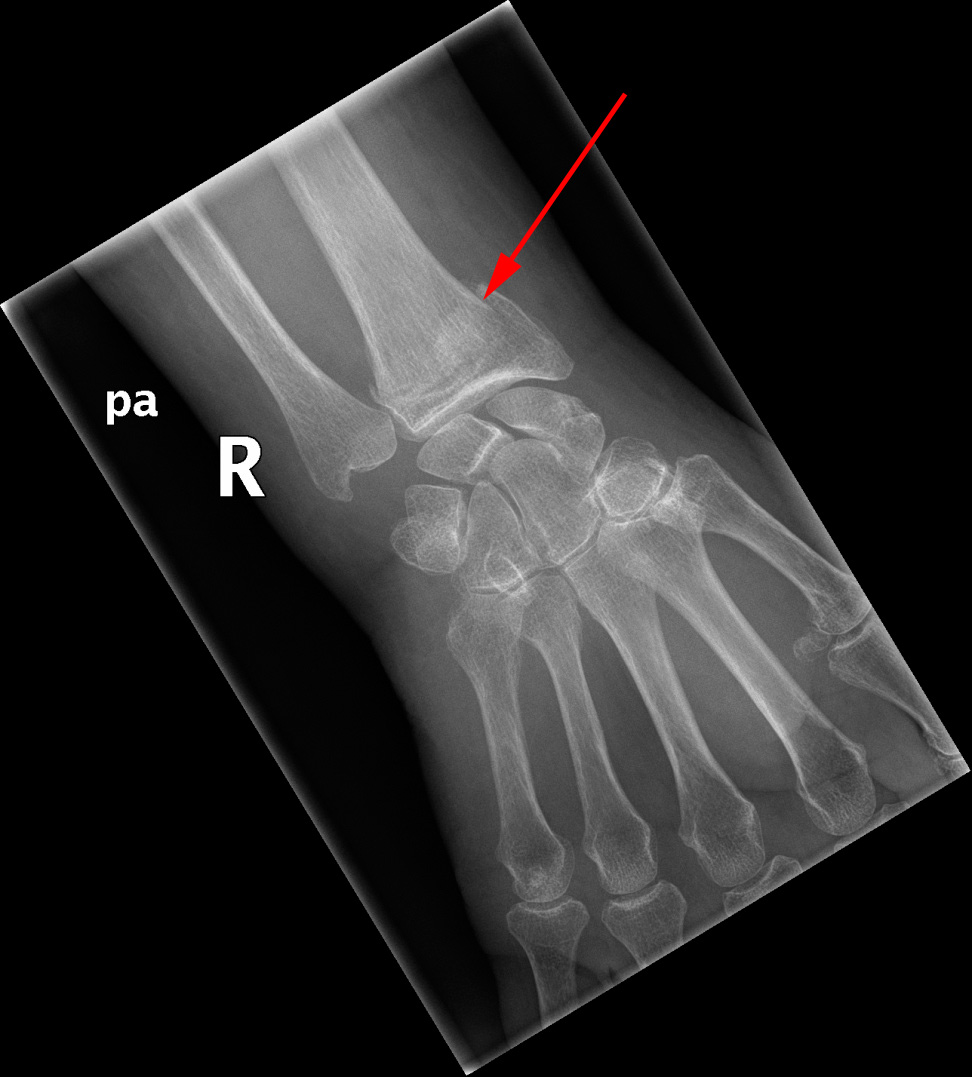

Røntgenundersøgelse af hånden viser distal radius fraktur (røde pil)